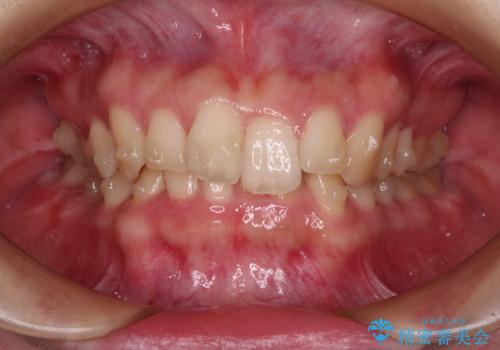

- 全体的な歯列の叢生を気にして来院された患者様です。

奥歯の咬み合わせを見ると、片方は上顎が下顎に対して相対的に前方にあり、他方は交叉した咬合の状態でした。

咬み合わせを改善するためには、上顎臼歯を後方に移動させた咬み合わせにする必要があります。